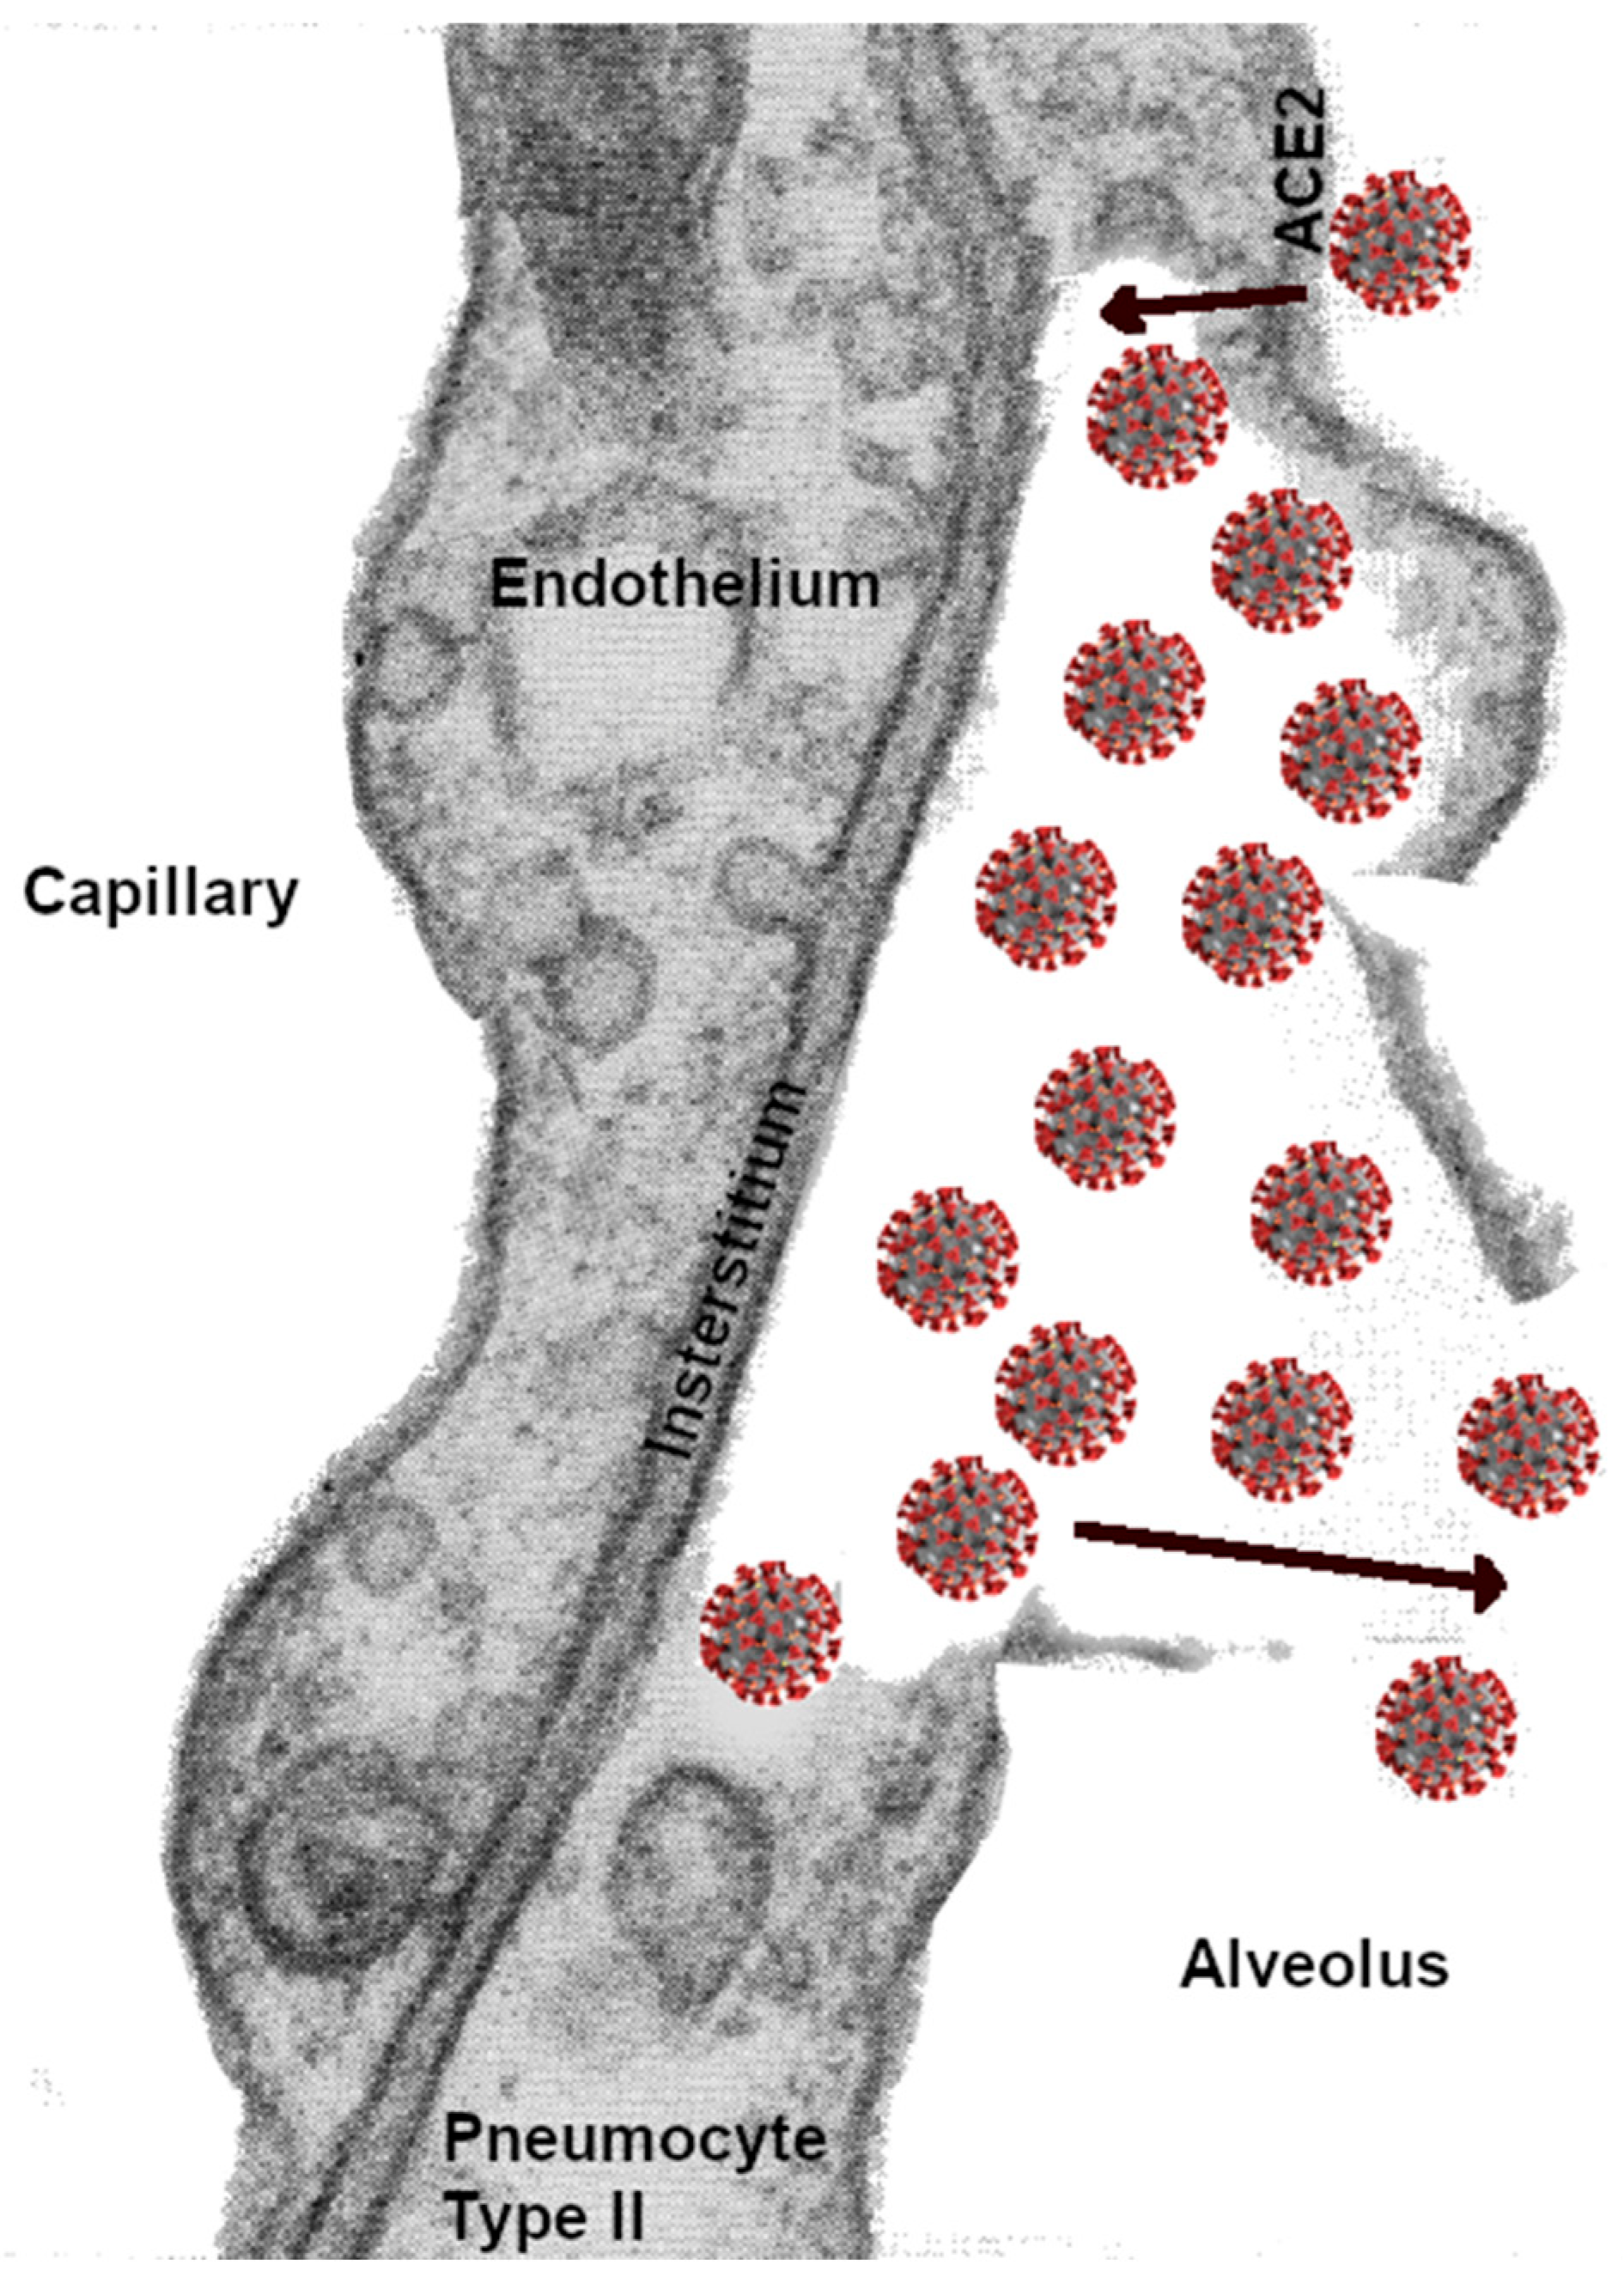

Figure 4.

Diagram depicting a possible scenario of SARS-CoV-2 reproduction within type II pneumocytes, inducing the rupture of the cellular wall and exodus of the coronavirus with replicated RNA, which migrate to infect other pneumocytes. The rupture of the pneumocyte wall would likewise induce alveolar capillary vasodilatation and possible entrance into the circulation and adhesion to endothelial ACE-2 receptors, resulting in coagulopathies. Coughing spreads the virus to other lung segments in both lungs and reduces the alveolar gas-exchange surface area.